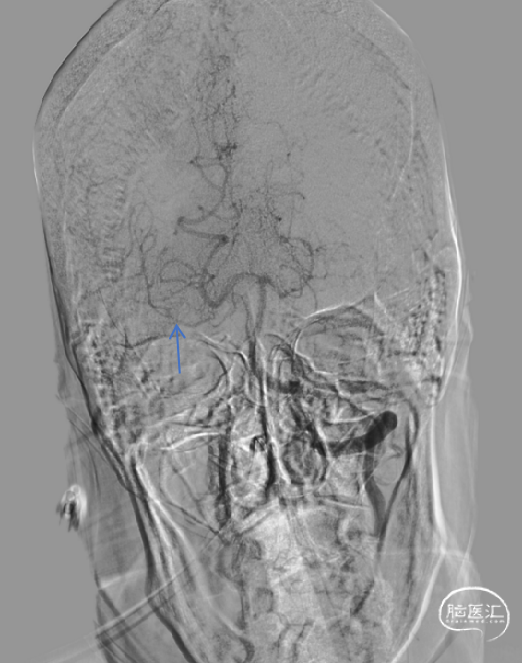

DSA评估:后交通开放(蓝色箭头),代偿至大脑中动脉供血区。

DSA评估:前交通开放,左侧大脑中动脉经软膜支逆向代偿至左侧大脑前动脉A2段,并经前交通代偿至右侧大脑中动脉供血区。

DSA评估:右侧颈外动脉未经眼动脉侧枝代偿。

DSA评估:右侧颈内动脉血流速度缓慢,C1段末端以远闭塞。

术前病情分析:DSA提示右侧颈内动脉C1段末端以远闭塞,局部可见“杯口”征;经前后交通代偿供血。结合心电图提示房颤,病因分型考虑为心源性栓塞可能性大。